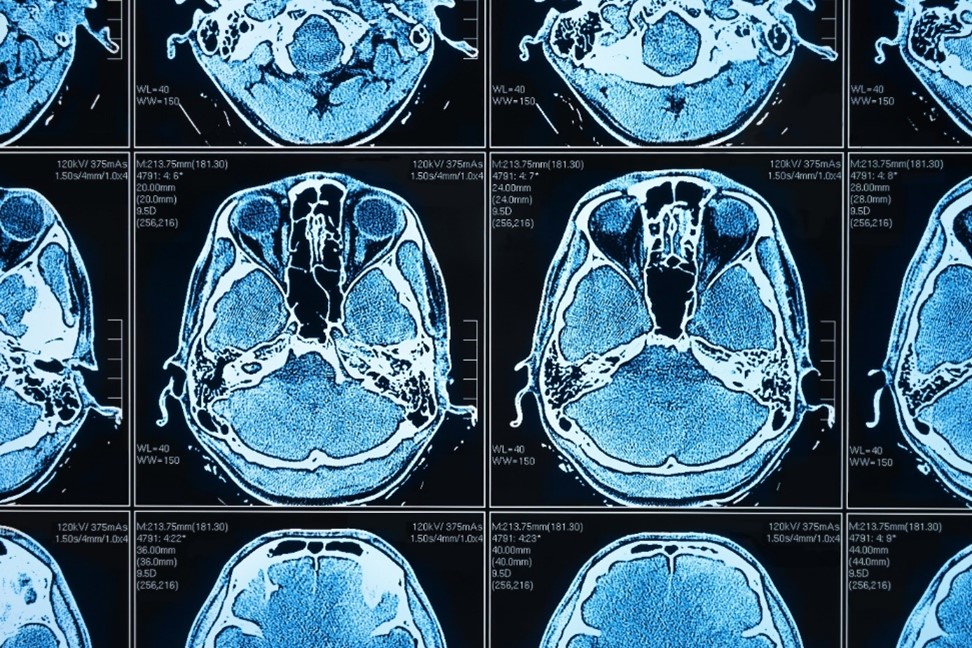

Künstliche Intelligenz (KI) und darauf gestützte Anwendungen werden in der medizinischen Praxis immer wichtiger. Und sie bieten unschlagbare Vorteile, beispielsweise in der Bildanalyse: Big-Data-Auswertungen und Massenverarbeitung von computergenerierten Dateien, Abgleich zwischen verschiedenen Datenbanken, Erkennung von Mustern und – fast noch wichtiger – von Abweichungen, Betrachtung von Entwicklungen im zeitlichen Verlauf, … die Liste der Anwendungsmöglichkeiten ist lang. Denn bei all diesen Aufgaben kann KI um ein Vielfaches effektiver und zuverlässiger „agieren“ als der Mensch.

Künstliche Intelligenz stellt eine ideale Ergänzung bei all jenen Aufgaben dar, die hohe Präzision und Effizienz erfordern. Gerade im Gesundheitswesen und insbesondere bei der Auswertung von bildgebenden Verfahren finden sich hier praktische Anwendungsszenarien en masse. Zudem ist künstliche Intelligenz bekanntlich trainierbar: Machine-Learning-Modelle erlauben es, große Datenvolumina in KI-Anwendungen einzuspeisen und diese entsprechend anzulernen, um zum gewünschten Abstraktionsniveau und damit zu belastbaren Ergebnissen zu kommen. Mit jedem neuen Datensatz wird die KI praktisch intelligenter und damit genauer.

Damit KI erfolgreich eingesetzt werden kann, braucht es umfangreiche und heterogene Trainingsdaten. Ein zuverlässiges Krebserkennungsmodell sollte beispielsweise auf der Grundlage von Tausenden von medizinischen Bildern trainiert werden, die gesundes Gewebe und Tumore im Vergleich aufzeigen können. Zugleich sollte das Modell auch die reale Bandbreite von Geschlecht, Alter und anderen demografischen Merkmalen der Patient*innen repräsentieren. Auch müssen visuelle Merkmale, die sich aus den verschiedenen Bildgebungstechniken ergeben, dargestellt werden.

In diesem ausführlichen englischsprachigen Artikel erfahren Sie mehr über die Hintergründe und können sich anhand eines fiktiven Demoszenarios zur Erkennung von Lungenentzündungen in Röntgenbildern über die Vorteile informieren.